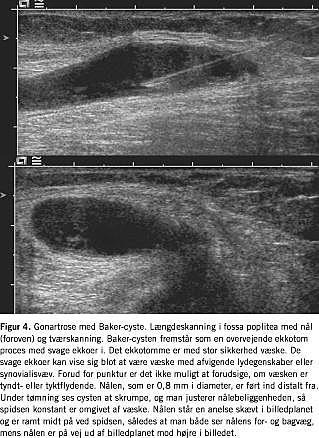

Baker-cyster og tilsvarende hernierende strukturer er overvejende lokaliseret omkring knæ, men findes også omkring albuer med forskellige dissektionsretninger i forhold til leddene (Fig. 4 ). Ultralyd anvendes bl.a., når nålens placering ved ledinjektioner og under tømning af disse cyster skal bestemmes, og ultralyd anvendes også til styring af en evt. ændring af nålebeliggenheden for at undgå tilstopning af lumen pga. indsugning af debris, septa eller ledkapslen (Figur 4). Forbindelsen fra cysterne ind til leddet ses kun i få tilfælde klart.